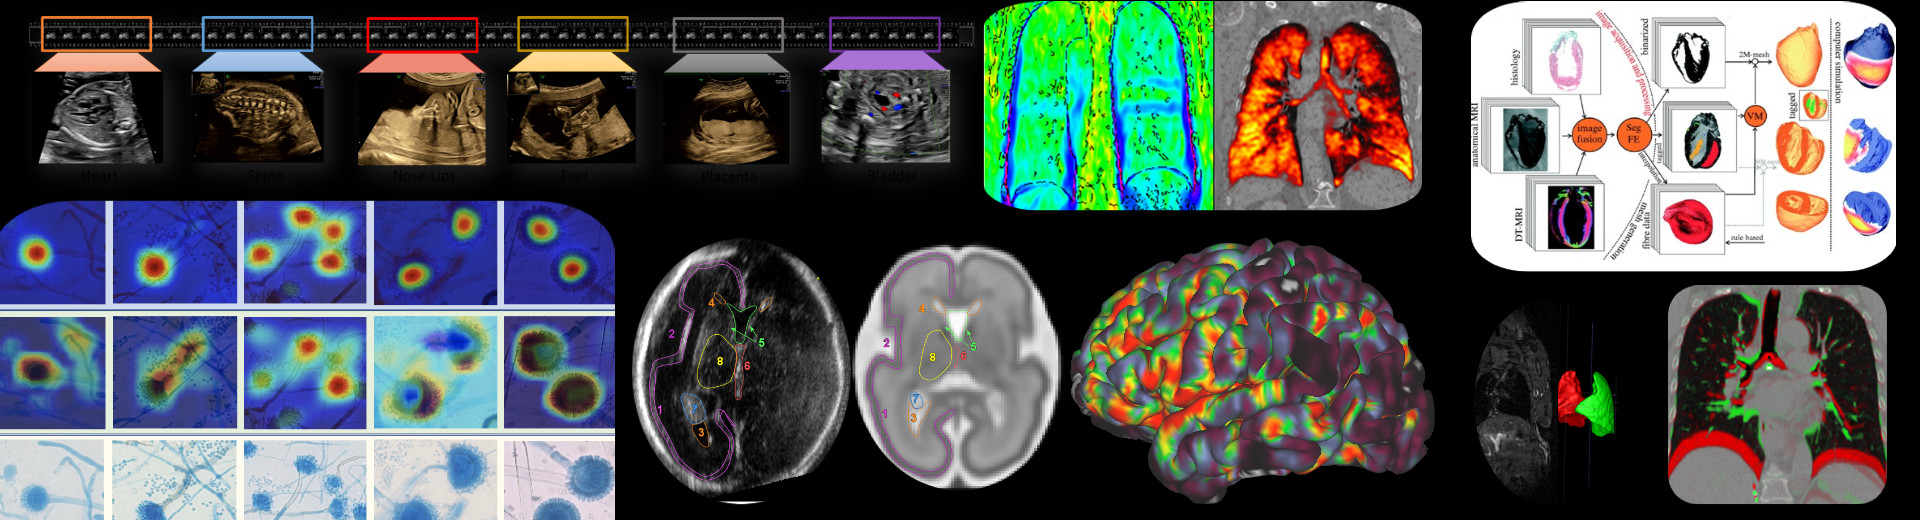

The Oxford Biomedical Image Analysis (BioMedIA) cluster is an academic group of faculty, postdoctoral researchers, software engineers, support staff and research students that develop medical imaging and image analysis algorithms and tools that aim to improve image-based diagnostics, therapies and monitoring technologies in hospitals and primary care, and for both western world and global health care settings. The breadth of our interests span all major clinical imaging modalities (particularly magnetic resonance imaging, ultrasound imaging, endoscopy imaging, histopathology), multi-modal imaging (imaging and audio, imaging and gaze tracking, imaging and electrocardiogram) and microscopy.

We conduct inter-disciplinary translational research with clinical partners in Oxford and elsewhere in the UK and overseas in clinical domains of application ranging from fetal development, to oncology, respiratory medicine, gastroenterology, neurology and cardiovascular medicine.

Bulte Group

We work on creating image acquisition We work on creating image acquisition and analysis methods for obtaining quantitative physiological information from both healthy and diseased tissue. We are particularly interested in imaging vascular pathologies, hypoxia in tumours, and neurodegeneration. Our research incorporates a variety of MRI techniques including Oxygen Enhanced MRI, arterial spin labelling, T1, T2 and T2 mapping, and diffusion imaging. In addition, we have ongoing research using transcranial Doppler ultrasound, near infrared spectroscopy, pupillometry, PET and CT. The group is working towards the clinical translation of these emerging methods, and thus we concentrate on using short, patient-friendly paradigms.

Grau Group

Our research focuses on the development of biomedical image analysis algorithms, with an emphasis on the combination with computational models, and applications on cardiac and pulmonary medicine.

Kamnitsas Group

We conduct advanced research on Machine Learning (ML) and Artificial Intelligence (AI) to develop the next generation of methods for medical image analysis. We push the boundaries of this technology to create more accurate, reliable and explainable methods. Our aim is to enable safe and effective use of ML/AI in healthcare, and apply this technology to tackle challenging clinical questions towards improving diagnosis and treatment.

Noble Group

The Noble group conducts research on machine learning applied to fetal ultrasound image analysis, cardiac magnetic resonance image analysis, and cell image analysis. A major focus of the group’s research is ultrasound. We are measuring at scale how operators scan, by recording eye and probe tracking, ultrasound video and audio in the clinic. This enables us to develop machine learning models to characterise operator skill, and to build multi-modal ultrasound assistive technologies to support non-experts to scan. We are also developing low-cost ultrasound technologies empowered by deep learning based algorithms for pregnancy risk assessment in collaboration with partners in Africa and India. Our overall ambition is to advance ultrasound towards it becoming an accessible medical imaging technology to all medical professionals worldwide.

Papiez Group

Motion is a massive barrier in cancer imaging hampering developments in cancer research and treatment. My research work has comprised the development of accurate, thus complex and realistic but still computationally efficient, models of organ motion, and has established a solid foundation to reliable quantitative cancer image analysis.

Rittscher Group

The aim of our research is to enhance our understanding of complex biological processes through the analysis of image data that has been acquired at the microscopic scale. We develops algorithms and methods that enable the quantification of a broad range of phenotypical alterations, the precise localisation of signalling events, and the ability to correlate such events in the context of the biological specimen.